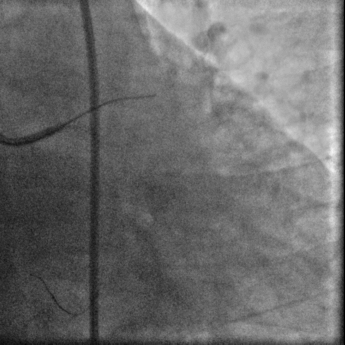

冠脉造影:

右足